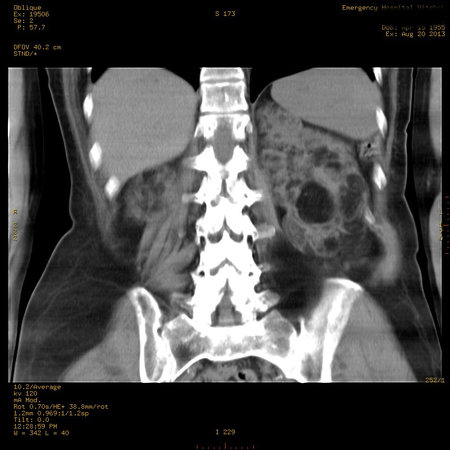

Пожилая женщина с нормальными мочевиной и креатинином.

Ангиомиолипоматоз почек , думаю компонент туберозного склероза.

Да, туберозный склероз.

Случай консультирован на кафедре радиологии Католического университета г.Лёвен (Бельгия) - зав каф. профессор Р.Оуен.